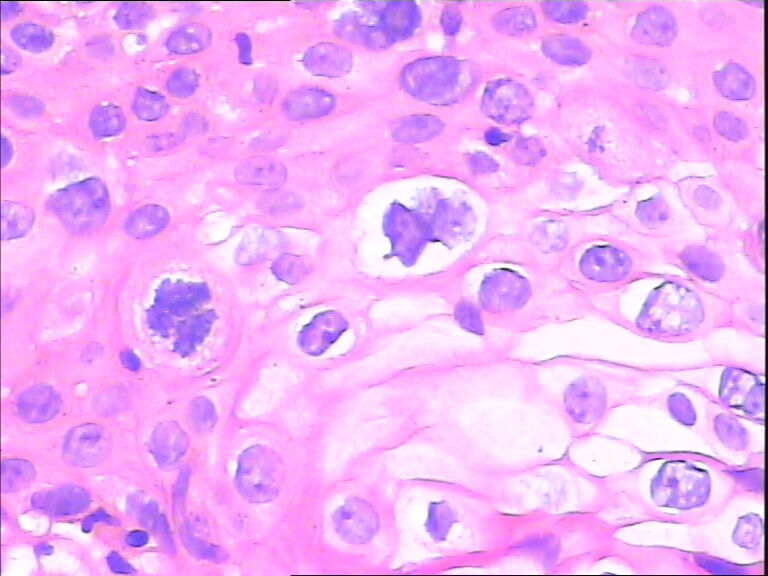

45y,触血,宫颈多点活检。